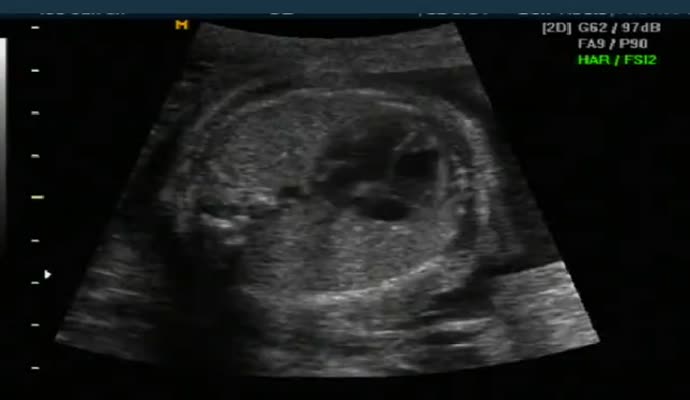

아래는 초음파 영상이기는 하지만 그렇게 올려진 영상 샘플입니다.

ob_usg_normal.mp4.jpg (17.74 KB, 다운수: 483)

ob_usg_normal.mp4

5.07 MB, 다운수: 872